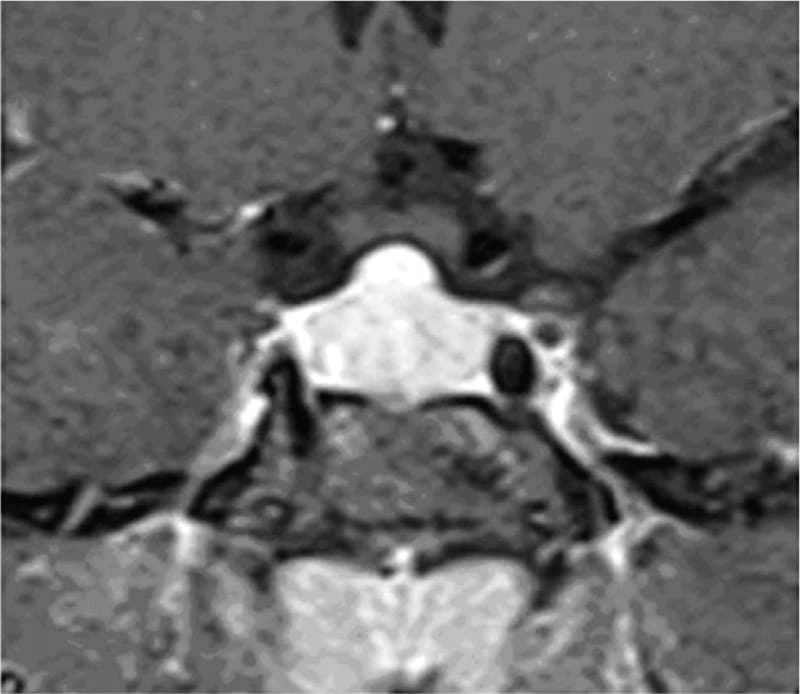

কেস ৩: এই কেসে, ২৪ বছর বয়সী এক তরুণীকে পিটুইটারি টিউমার সন্দেহে অপারেশন করা হয় এবং পরদিন হরমোনাল চিকিৎসার জন্য রেফার করা হয়, যিনি অপারেশনের পর ডায়াবেটিস ইনসিপিডাসে আক্রান্ত হন। পরবর্তী বিশ্লেষণে তার প্রি-অপারেটিভ TSH ছিল অনেক বেশি এবং MRI তে “ডোম-আকৃতির” পিটুইটারি বড় হওয়া দেখা যায়। অপারেশন এড়ানো সম্ভব হলে, এ রোগীও ওষুধেই সুস্থ হতে পারতেন। এরকম টিউমার সন্দেহে অপারেশনের নিদর্শন বিশ্বযুরে একাধিক রয়েছে এবং বলাবাহুল্য এ ধরনের অপ্রয়োজনীয় অপারেশনের পরে রুগীরা আজীবন বন্ধ্যাত্ব এবং একাধিক হরমোন ঘাটতির কারণে জীবনভর ভুগতে হয়। ভাগ্যক্রমে, এই রোগীটির ক্ষেত্রে অপারেশনের পর তিনি কোনো স্থায়ী নিউরো-হরমোনাল ঘাটতিতে পরেননি।

MRI-তে এই হাইপারপ্লাসিয়া সাধারণত গম্বুজ-আকৃতির ও সমমিত হয় এবং হোমোজেনাস সিগনাল ইন্টেনসিটি দেখায়, যেখানে সাধারণ নন-ফাংশনাল পিটুইটারি অ্যাডেনোমা নানা আকার ও অসমতা নিয়ে দেখা যায়।

তাঁর দাবি, MRI-তে ‘DOME Sign’ থাকা এবং TSH বাড়তি থাকলে, সেটি হাইপোথাইরয়েডিজম-জনিত হাইপারপ্লাসিয়ার সম্ভাবনার কথা নির্দেশ করে এবং এই রোগীদের শুধুমাত্র লেভোথাইরক্সিন দিয়ে চিকিৎসা করলে পূর্ণ আরোগ্য সম্ভব।